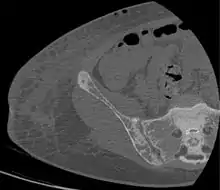

Brown tumors in the pelvis and a hip fracture.[13]

Subchondral resorption in the sacroiliac joint.[13]